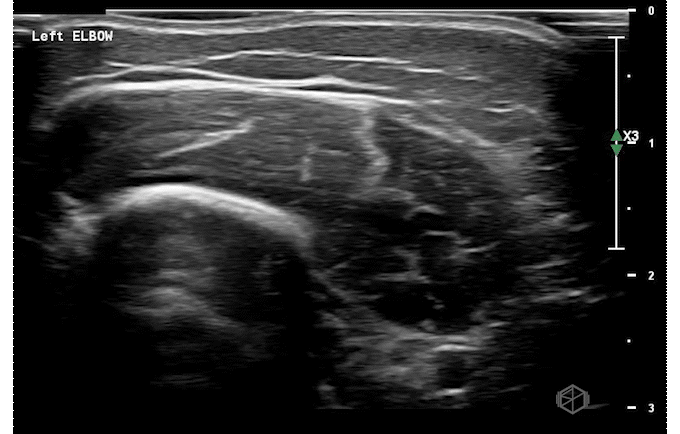

Our second SonoProp goes to Dr. Siri Tummala. Dr. Tummala scanned a 4-year-old male with LEFT elbow pain after injuring himself while going down a slide. Using the linear probe she obtained two views of the supracondylar area as seen below and compared it to the right elbow.

The LEFT elbow demonstrates an elevated fat pad with heterogeneous material within it representing lipohemarthrosis, while the right elbow demonstrates a normal posterior fat pad.

Diagnosis — Left elbow supracondylar fracture

• Ultrasound has high sensitivity (98-100%) and specificity (70-93%) for a supracondylar fractures (23142008, 26815896, 27277459). Lipohemarthrosis, a prominent dorsal fat pad are highly indicative of supracondylar fractures. Cortical disruption can be seen as well. When XR and US are both negative, the possibility of fracture can be rule out definitively (27697406).

• While it does not replace X-ray, ultrasound can be used when there is a high suspicion and the X-ray is equivocal or read as negative to diagnose occult supracondylar fractures.